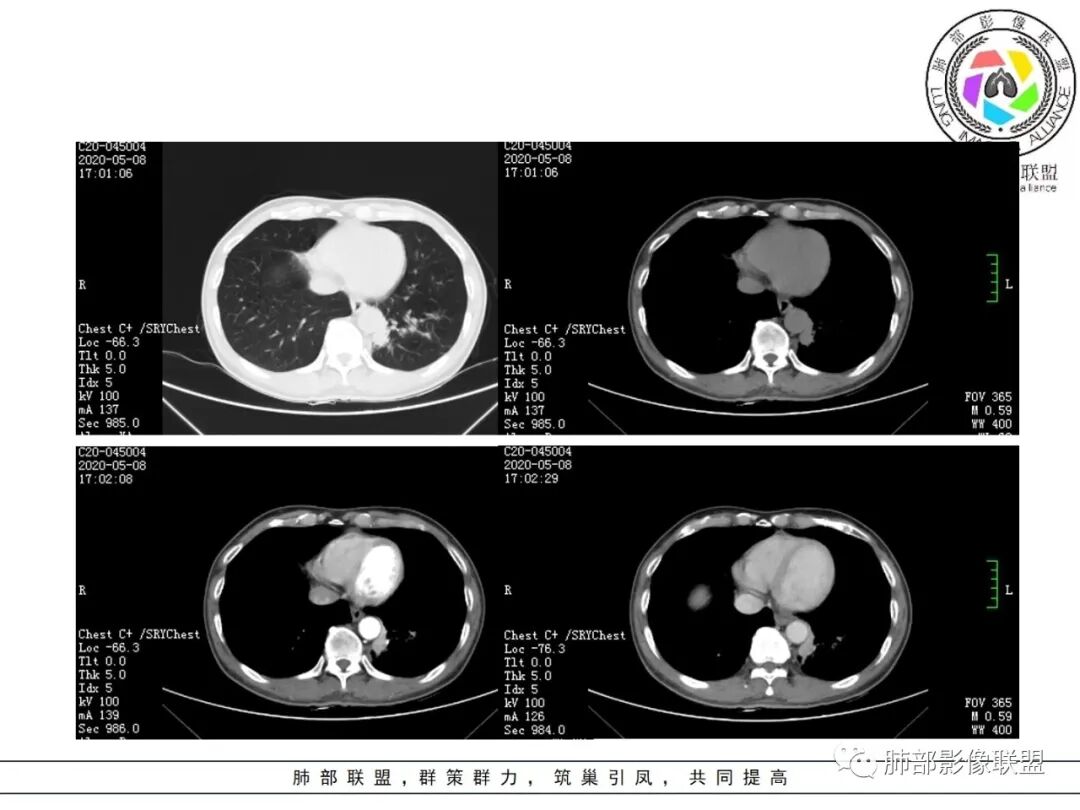

临床资料:老年男性,咳嗽咳痰2月余,慢性病史。有吸烟史40年(现已戒烟),抗感染治疗2周肺部病灶未见吸收。

影像所见:

肺气肿背景。

结节伴分叶。

斑片影,考虑阻塞性炎症。

支气管壁厚,支气管腔内高密度影填充。

周围散在斑片影及结节影,类似“小花花草草”的感觉。